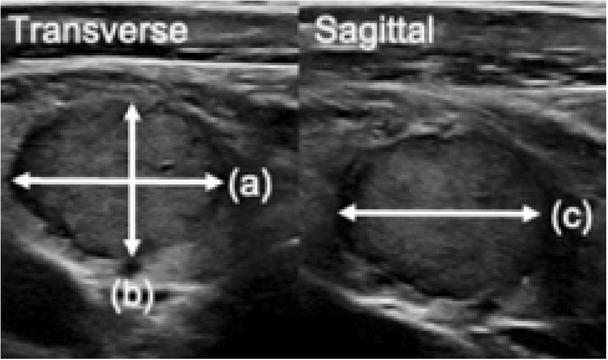

The nodule size should be measured in three dimensions (a × b × c) (Fig. 9). On a transverse sonogram of the thyroid, obtain the dimension of the nodule along its longest axis (a) followed by its largest dimension on a perpendicular plane to this (b). Next, on a sagittal sonogram of the thyroid, obtain the largest cranio-caudal dimension (c)(3, 4). Calculating the volume of a nodule (formula = 0.52 × a × b × c) should also be performed, as this can provide a better indication of nodule enlargement compared to assessing measurements in three dimensions separately(13).

Fig. 9

Greyscale sonographic images of a thyroid nodule, demonstrating how to measure nodule size, (a) × (b) × (c)